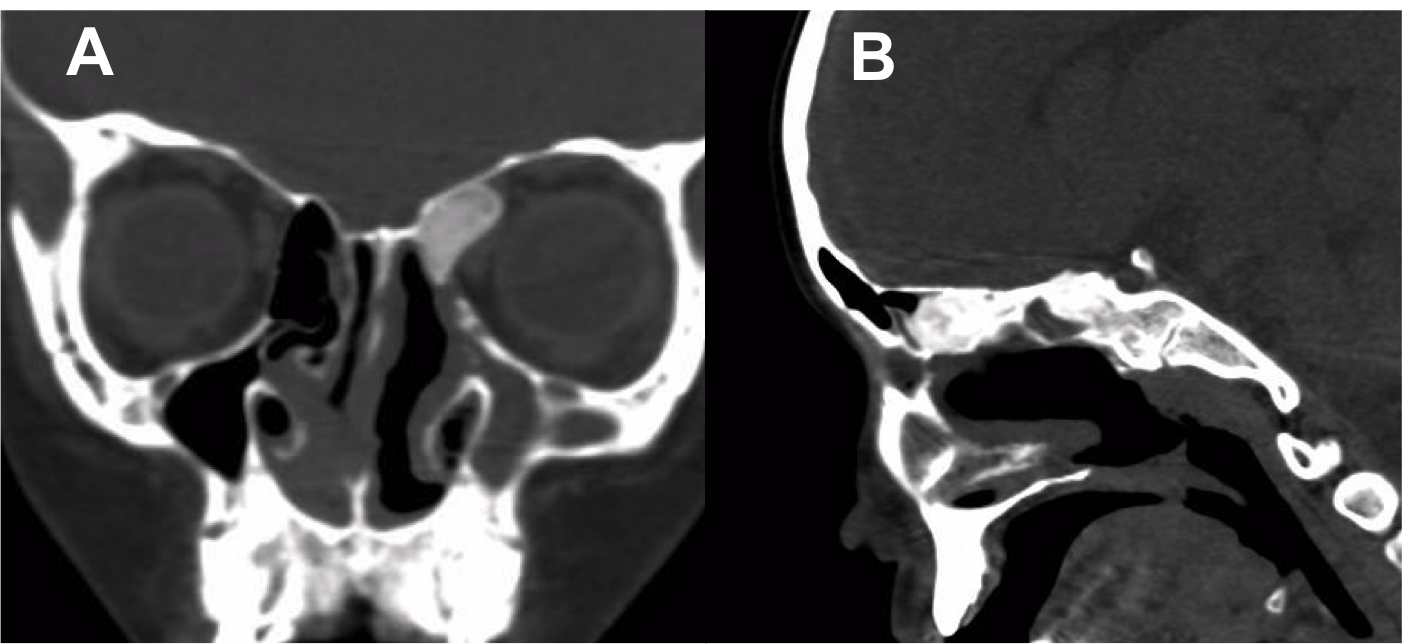

Resultados: Fueron intervenidos 8 pacientes entre los 2 y 14 años, con una edad promedio de nueve años y un seguimiento promedio de 16 meses. En el 75% se hizo una resección total del tumor. Un paciente requirió una reintervención y un paciente fue sometido a radiocirugía post-operatoria. 1 paciente falleció a pesar de múltiples intervenciones, quimioterapia y radioterapia.